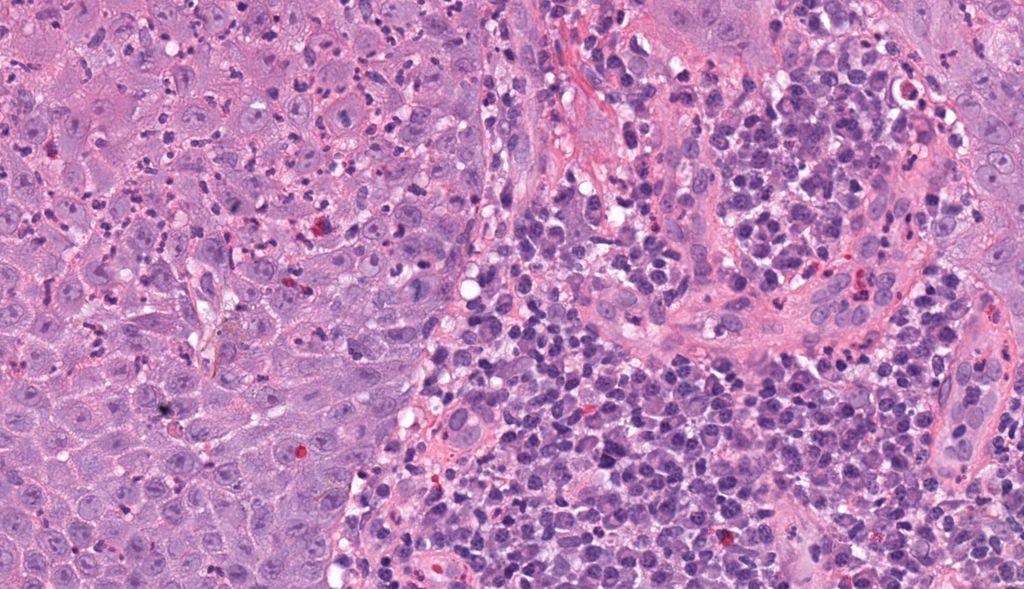

Bx for progressive CKD in a pt with CML, in remission. Limited biopsy with prominent debris filled proximal tubule lysosomes + for lysozyme (no evidence for light chain restriction (F/P) or chromogranin). Suspicious for lysozyme nephropathy . #renalpath #pathtwitter #nephrology